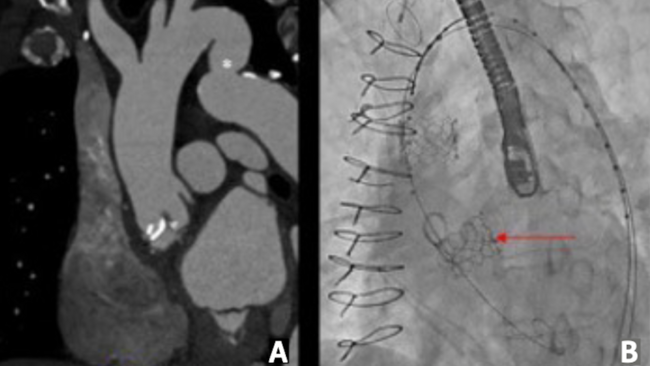

Echocardiography demonstrated severe bioprosthetic AV stenosis (mean gradient, 50 mm Hg; aortic valve area, 0.84 cm2) and moderate AV regurgitation. Valve-in-valve transcatheter aortic valve replacement with a Sentinel cerebral protection device (Boston Scientific) was recommended. Preoperative computed tomography scan showed dilated aortic root and descending aorta with evidence of pseudocoarctation (Figure 1A).

A 23-mm Edwards Sapien 3 valve (Edwards Lifesciences) was deployed. Before the valve was fully expanded, it embolized into the aortic root due to stored tension (Video 1). Attempts to insert the valve inside the prosthetic valve were unsuccessful. An additional 23-mm S3 valve was advanced through the embolized valve and was successfully deployed (Figure 1B). In order to stabilize the first S3 valve, an uncovered 36- x 120-mm dissection stent was implanted via an extra-stiff Lunderquist wire (Cook Medical). A TriLobe balloon (Gore) was advanced over the wire and inflated within the embolized valve to ensure appropriate stent apposition (Figure 1C). A final angiogram showed good flow into the aorta and good stent apposition (Figure 1D).